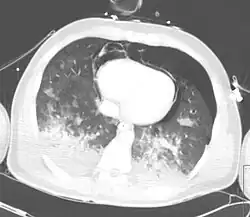

CT-Thorax Aufnahme eines Patienten nach Thoraxtrauma mit Pneumothorax, Hämatothorax, Pneumomediastinum und Pneumoperikard.

Ein Hämatopneumothorax tritt auf bei Thoraxtraumen oder iatrogenen Lungenverletzungen. Hierbei kommt es zu einer Kombination aus einem Hämatothorax und einem Pneumothorax.